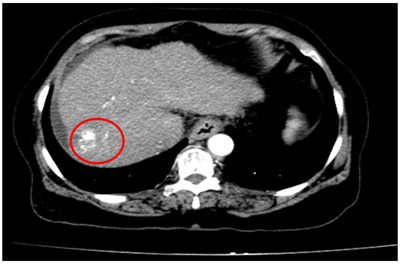

Ca lâm sàng:Hiệu quả điều trị đích bằng Osimertinib ở bệnh nhân UT biểu mô tuyến của phổi giai đoạn IV có đột biến gen EGFR L858R (Exon 21) tại Trung tâm YHHN&UB-Bệnh viện Bạch Mai